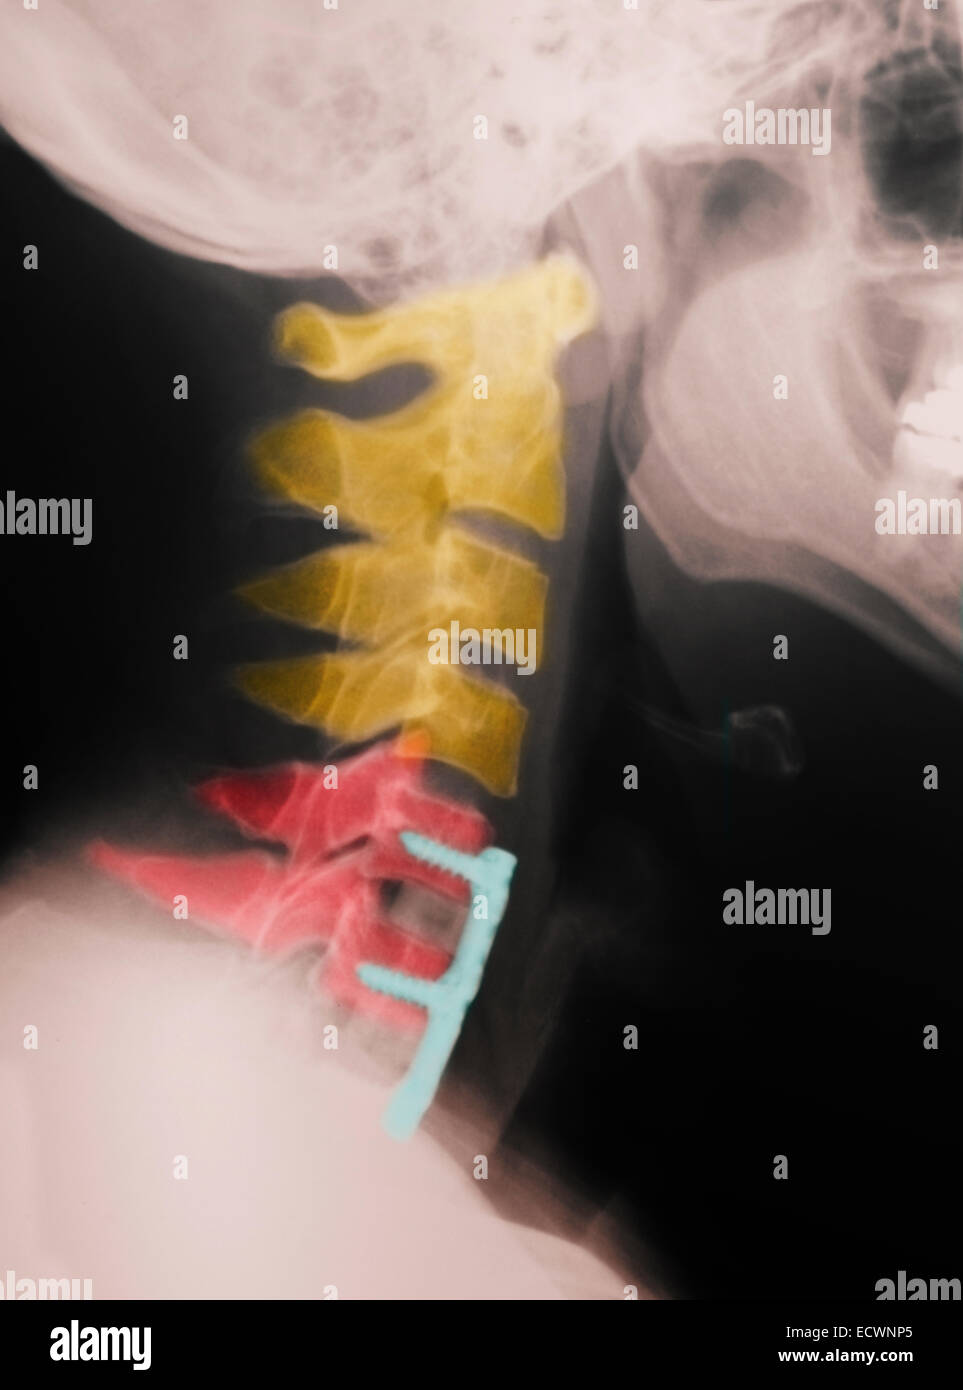

WebConsejos para el postoperatorio de artrodesis lumbar 1-Pasee: paseos cortos y frecuentes Camine cada día cortas distancias y auméntelas cada día de manera progresiva.. WebLa columna cervical, región anatómica donde se origina esta patología, está formada por siete vértebras y discos intervertebrales, y el desgaste se crea en las articulaciones. WebJunto a la rehabilitación,para que la evolución sea favorable a largo plazo,es importante que el paciente conozca, que debe evitar levantar pesos excesivos,ya que es una de las. WebTendrá que usar una ortesis (corsé) después de la cirugía para mantener estable la columna y promover la cicatrización durante 2 meses. En cama podrá retirarla. Se tarda. WebLa artrodesis cervical posterior no requiere quitar el disco intervertebral, para realizar la fusión vertebral usaremos tornillos y barras. COMPLICACIONES DE LA. WebSi la hernia era cervical entenderá que tampoco podrá trabajar de forma inmediata por lo que quizás tendrá que usar analgésicos y opiáceos que le evitarán.

WebLa artrodesis cervical posterior no requiere quitar el disco intervertebral, para realizar la fusión vertebral usaremos tornillos y barras. COMPLICACIONES DE LA. WebSi la hernia era cervical entenderá que tampoco podrá trabajar de forma inmediata por lo que quizás tendrá que usar analgésicos y opiáceos que le evitarán.